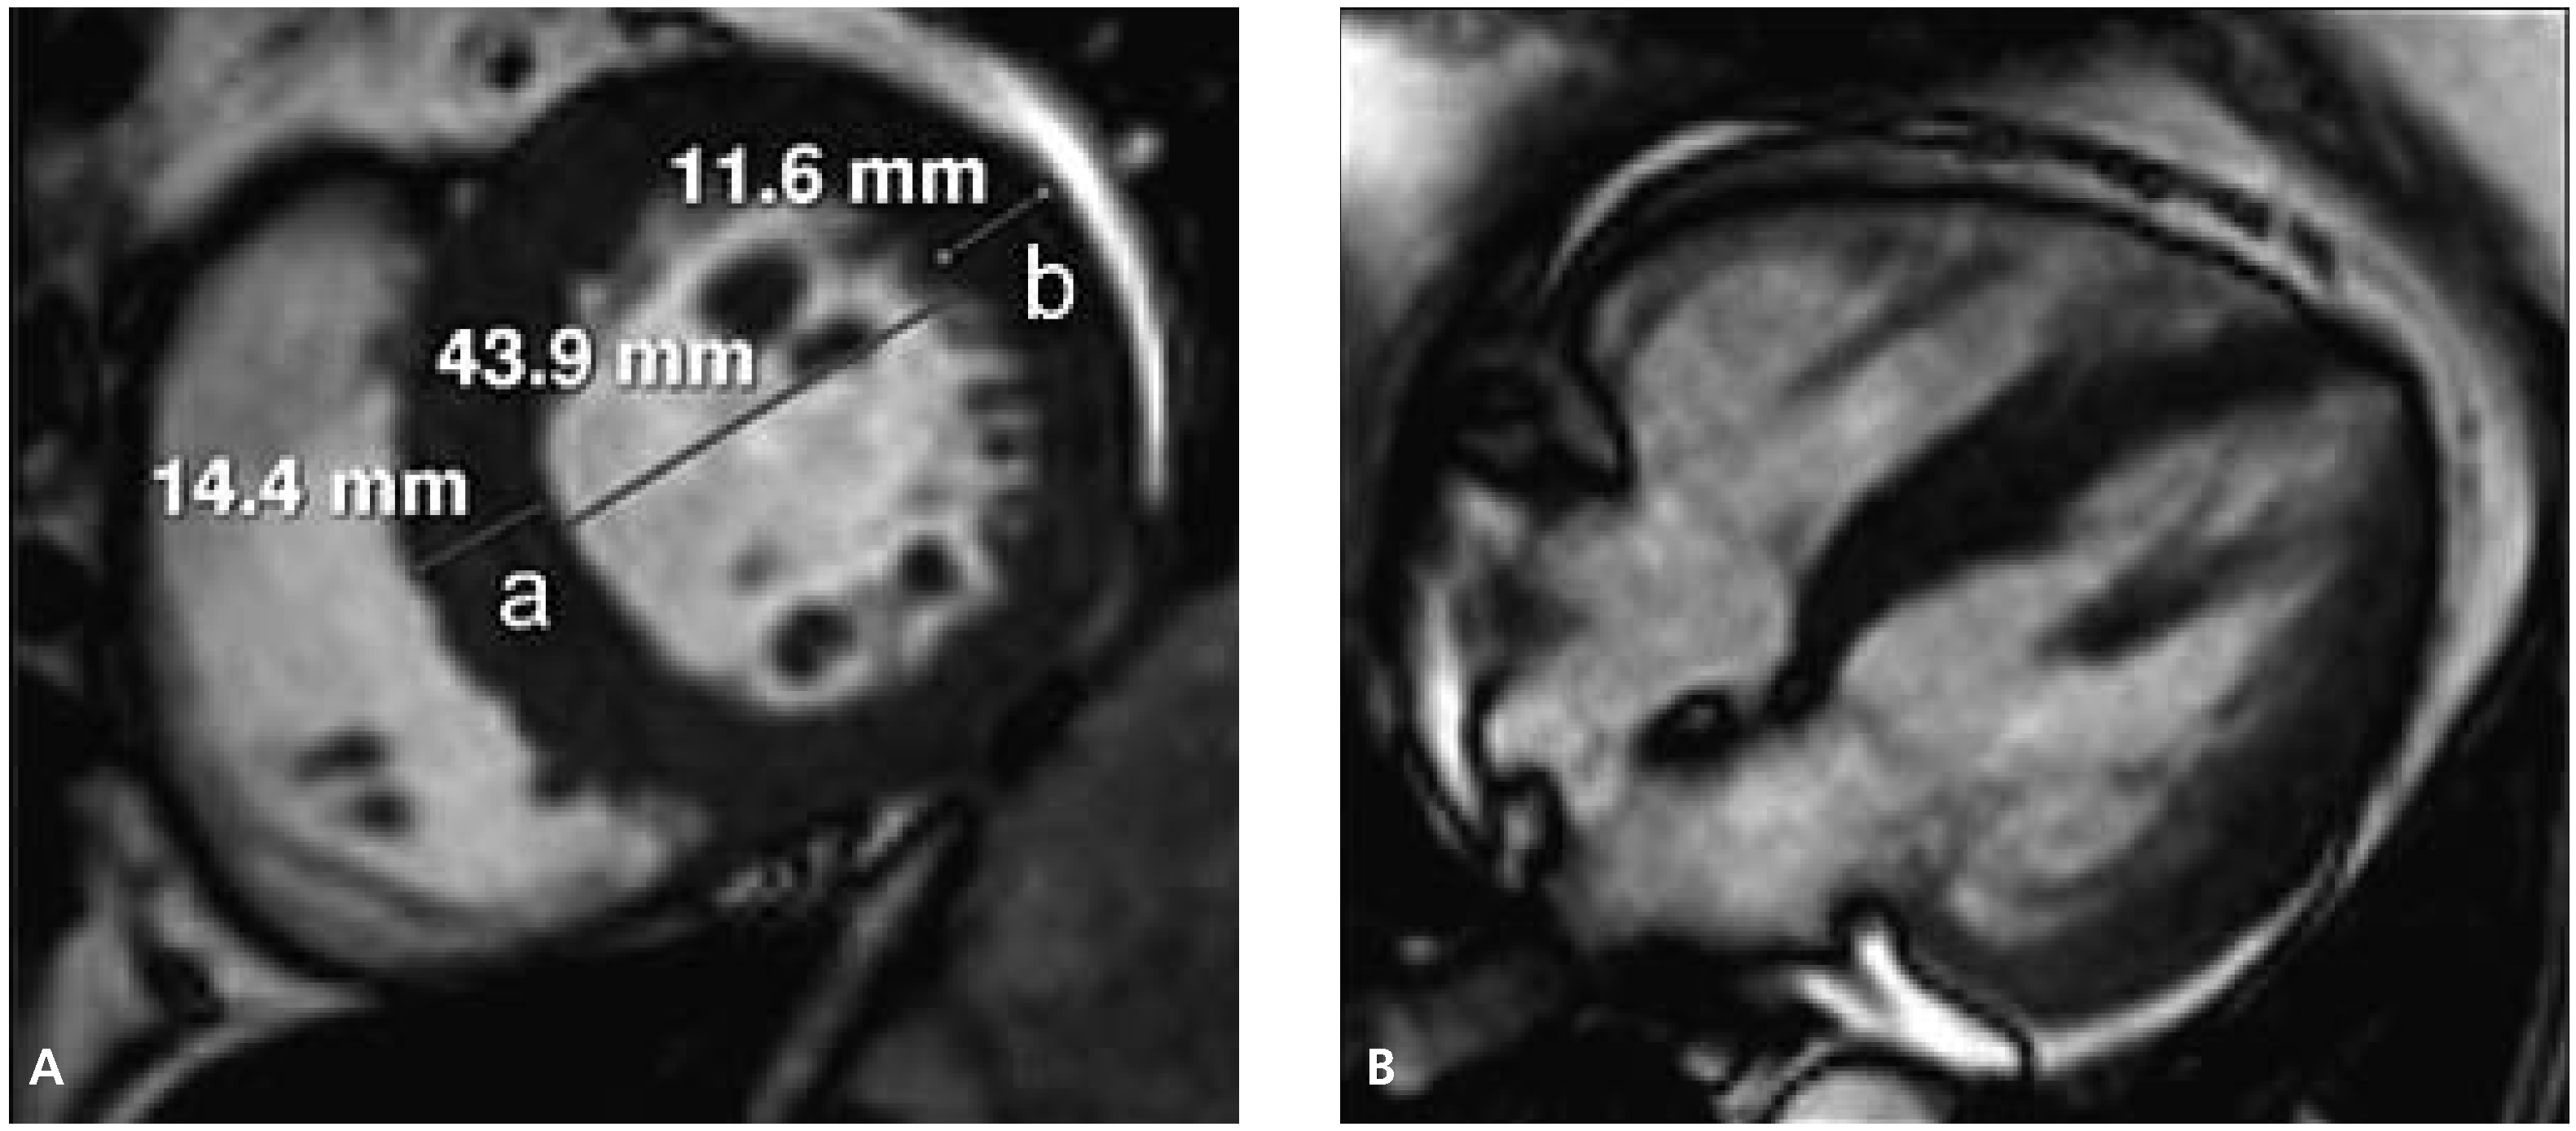

Abbildung 3.

Initiale Darstellung der rechten und linken Nierenarterie zur Überprüfung der Anatomie vor Durchführung der renalen Sympathikusdenervation.

Die Durchführung der renalen Sympathikusdenervation erfolgte im standardmässig eingerichteten Herzkatheterlabor unter monoplaner Durchleuchtung. Die Vorbereitung der Patientin entsprach im Wesentlichen der einer Koronarangiographie. Nach lokaler Anästhesie der vorgesehenen Punktionsstelle erfolgte die Punktion der linken Arteria femoralis. Mittels Seldinger-Technik wurde eine 8-French-Schleuse in das Gefäss eingeführt. Anschliessend erfolgte nochmals die Darstellung der renalen Gefässanatomie (Abb. 3). Es zeigte sich entsprechend dem magnetresonanztomographischen Vorbefund eine geeignete Anatomie beider Nierenarterien. Nun wurde ein 8-French-LIMA-Führungskatheter eingebracht und die linke Nierenarterie intubiert. Über einen Führungsdraht (BMW, Abbott Laboratories, Illinois, USA) wurde in der Folge ein 5-F-Multipurpose-Katheter bis zur Bifurkation der Nierenarterie eingeführt. Nach Rückzug des Führungsdrahtes wurde über den liegenden 5-F-Katheter der Symplicity™-Ablationskatheter in der linken Nierenarterie platziert. Danach wurde der 5-F-Katheter zurückgezogen und ein Kontakt der Spitze des Ablationskatheters mit der Nierenarterienwand hergestellt (Abb. 4).